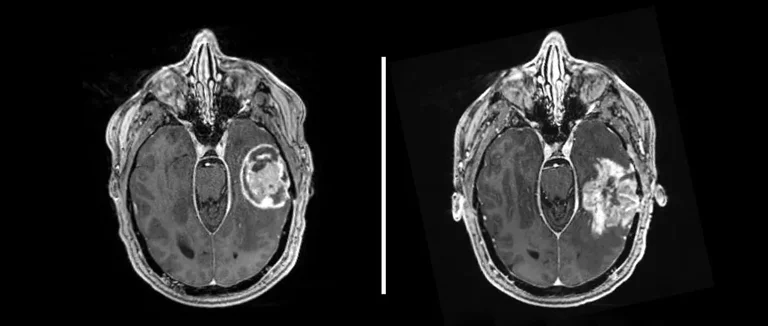

L'IRM Fonctionnelle (IRMf)

L'IRM fonctionnelle (IRMf) détecte les changements dans le flux sanguin liés à l'activité neuronale. Elle cartographie les régions du cerveau actives, que ce soit lors de tâches ou au repos. L'IRMf aide à comprendre comment notre cerveau se concentre.

Les avantages de l'IRMf sont :

● Une haute résolution spatiale

● La capacité de cartographier l'activité cérébrale en temps réel

● Une méthode non invasive